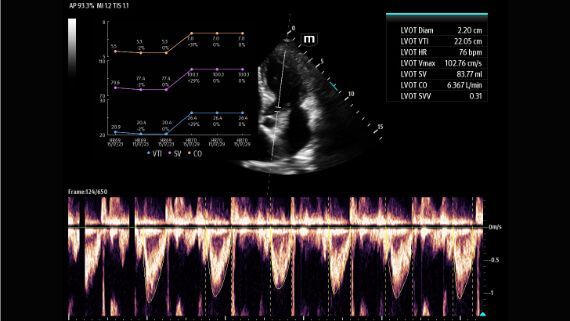

X-Pilot: Clinical Application-Oriented Workflow

Based on the professional society guidelines for point of care ultrasound, the X-Pilot suite integrates historical diagnostic images and multi-organ data into a concise and precise view of the patient status to support rapid clinical decisions at the bedside.